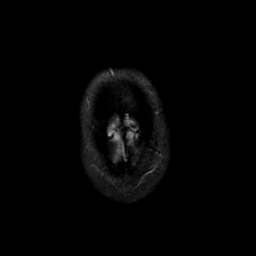

MR Study #21, November 3, 1991 -- Slice #48

[Home][Help][Clinical][Tour 1][Tour 2] Slice 48